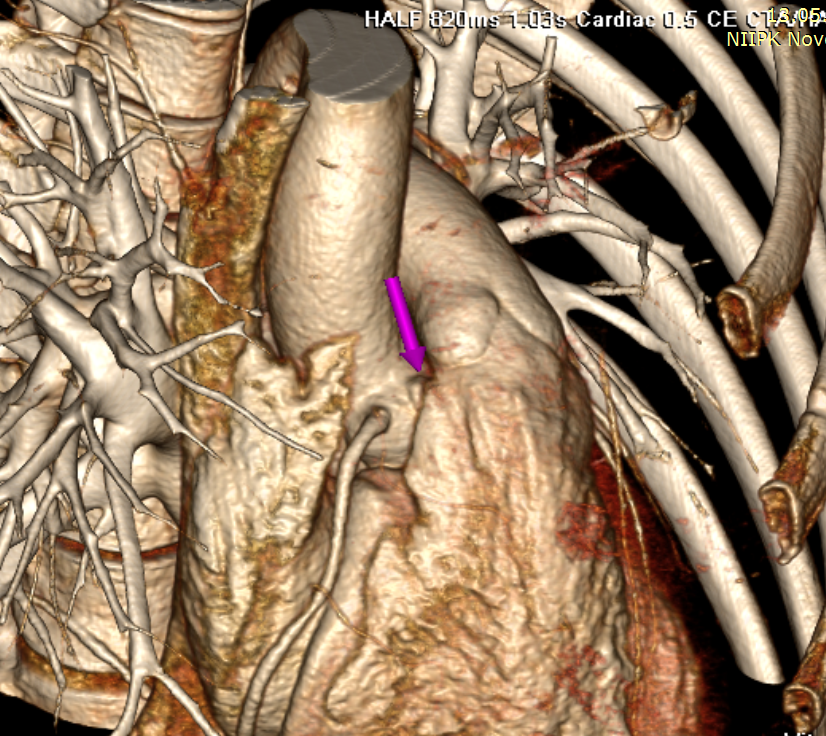

Выполнено МСКТ исследовании с контрастом: определяется дефект между правым коронарным синусом Вальсальвы и ПЖ в области ВОПЖ. Расстояние от края дефекта до устья правой коронарной артерии – около 3,0- 4,0 мм. Размеры фистулы со стороны правого желудочка - 4,5х 5,0 мм, со стороны синуса аорты - до 6,0х 6,0 мм, протяженность стенок (длина канала дефекта): справа и слева - около 9,0 и 6,0 мм соответственно. (Рис 2.)

Рисунок 2.

На трехмерной реконструкции можно отметить, что устье правой коронарной артерии находится в близости "устья" аорто-правожелудочкового дефекта. (рис. 3)

Рисунок 3.